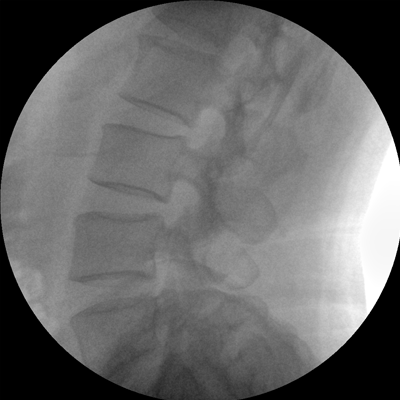

四維電動(dòng)運(yùn)動(dòng)控制,平滑定位,使得復(fù)雜角度快速實(shí)現(xiàn)。

專業(yè)的圖像處理系統(tǒng),為您提供高分辨率、高灰階圖像。